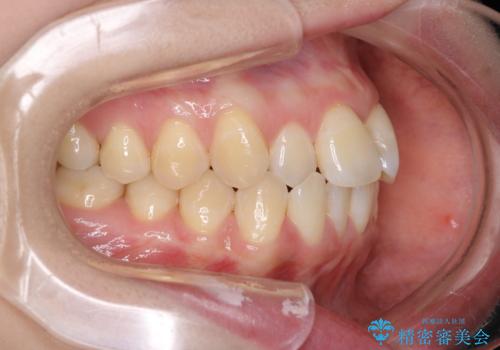

- メタル装置

- 前歯のがたつきを治したいという主訴で来院されました。1年後に転勤の可能性があり短期間での治療を希望されました。今回は非抜歯の治療を計画し、IPRと拡大をし、前歯の叢生を改善しました。

前歯のがたつきを治しながら2番の反対咬合も改善させました。短期間で終了し満足していただけました。